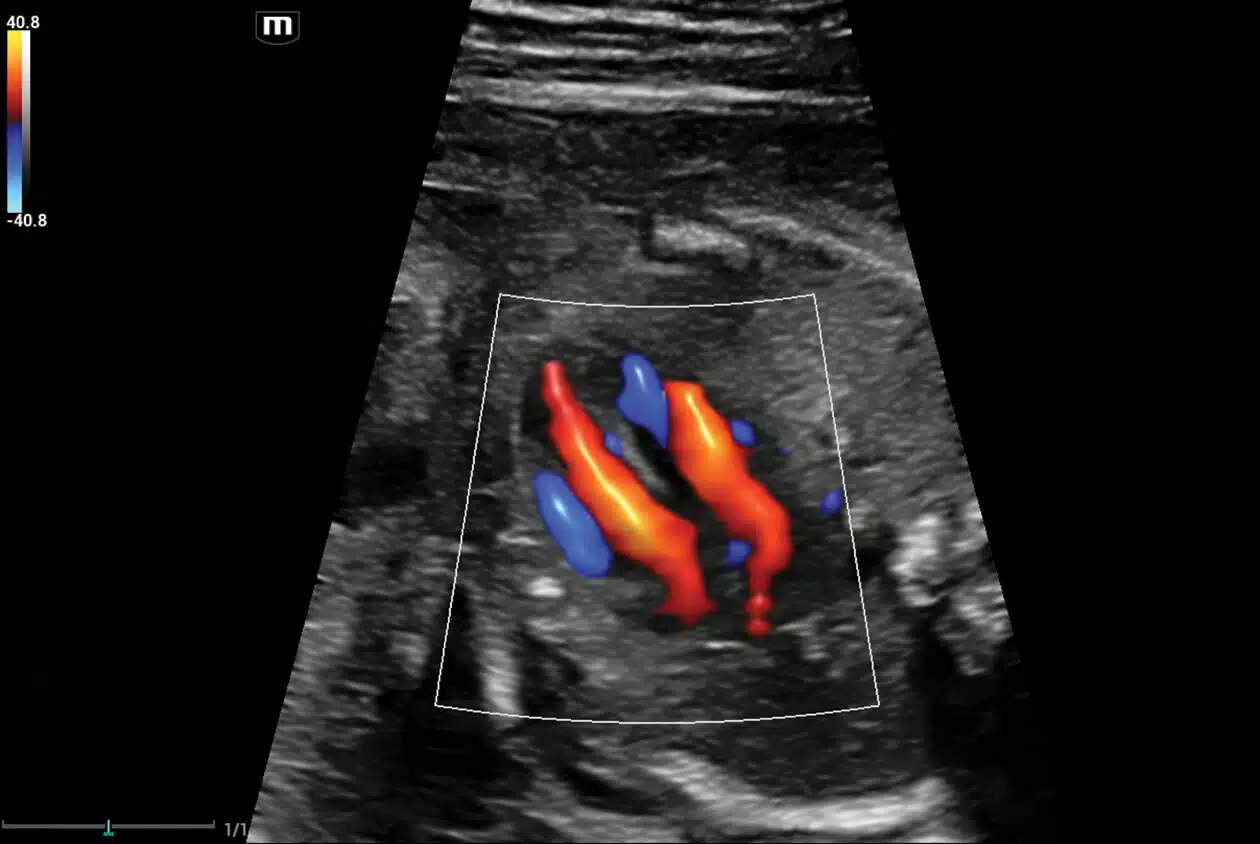

• Glazing-FLow-Fetal-Heart.jpg

Fetal Heart with Glazing Flow